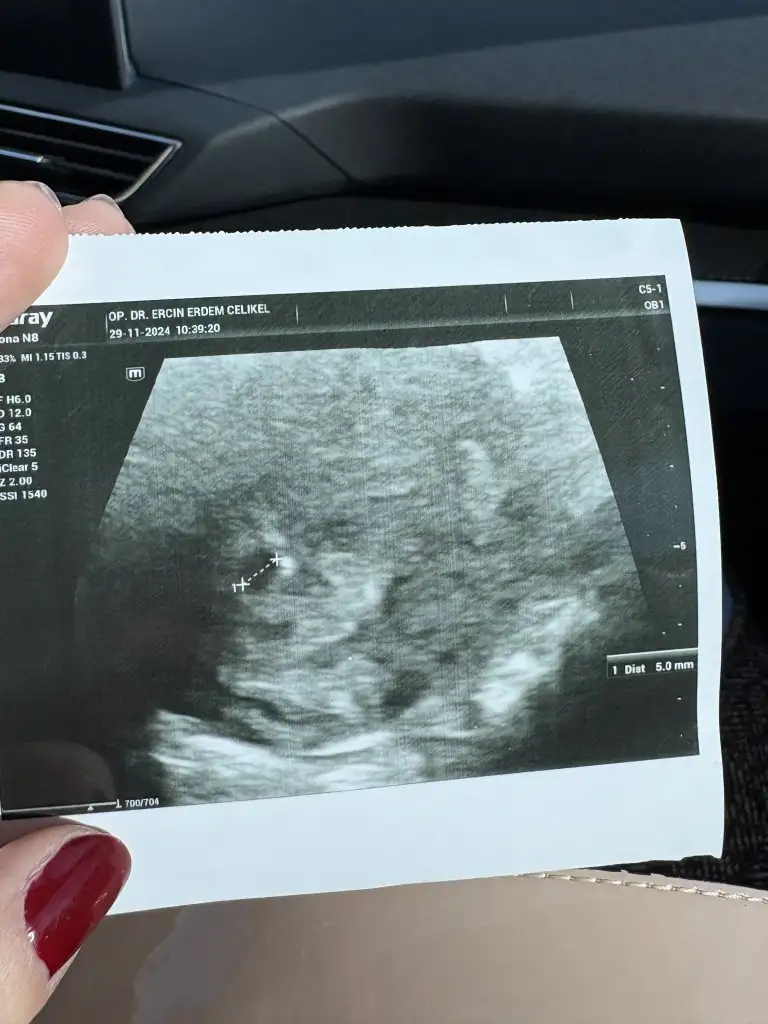

güzelim fotoğrafı böyle. 5mm dedi doktor. bence doktor bir sorundan bahsetmediyse sorun yokturKuzucum kesenin fotosu var mı ya. Benim kesem biraz uzun gibi geldi bana. Doktorum hiç bi sorun söylemedi aslında ama burada bi şeyler yazmışlar tedirgin oldum

Benimki de bu arada 8mm sende 5+0 da mı gittingüzelim fotoğrafı böyle. 5mm dedi doktor. bence doktor bir sorundan bahsetmediyse sorun yoktur

güzelim fotoğrafı böyle. 5mm dedi doktor. bence doktor bir sorundan bahsetmediyse sorun yoktur

Ay kuzular sizinki yuvarlak ya benimkine baksanıza olumsuz yorum yapmadı aslında ama forumda çok olumsuz yorum okudumBenimki de bu arada 8mm sende 5+0 da mı gittin

Kaç mm dedi doktor ? Bence gayet normal kuzum her kese farklıdırAy kuzular sizinki yuvarlak ya benimkine baksanıza olumsuz yorum yapmadı aslında ama forumda çok olumsuz yorum okudum

0.99 cm yazıyor kuzum. Normalde 5 de gitmiştim sata göre. Doktor kese götürüne göre tahminen 5+5 gibi dediKaç mm dedi doktor ? Bence gayet normal kuzum her kese farklıdır

Senin kesen benimkinden büyük kalp atışı için ne zaman gidiceksin0.99 cm yazıyor kuzum. Normalde 5 de gitmiştim sata göre. Doktor kese götürüne göre tahminen 5+5 gibi dedi